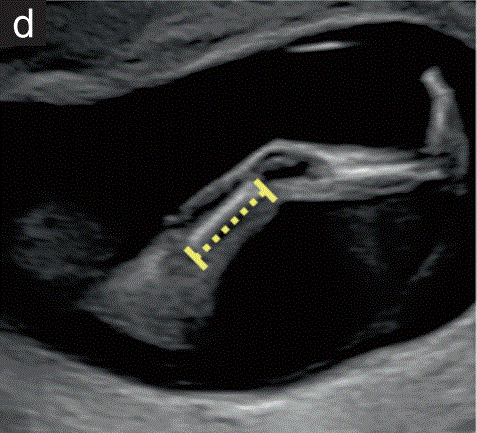

股骨测量(FL)

股骨长度在股骨长轴平面内测量(图1d)。卡尺放置在骨化骨干的两端,清晰可见。

进行这种测量的一个优点是,它可以确保超声医生检查下肢的发育情况,这可能会早期发现严重骨骼异常的存在。

胎儿mt是什么检查什么疼吗【文献学习/规范指南】ISUOG实践指南(2023更新): 11-14周胎儿超声检查(全文)_https://www.jmylbn.com_新闻资讯_第5张

图1 11+0至14+0周胎儿超声检查可获得的测量值。(d股骨长度测量。整个股骨干是可见的。卡尺放置在两端。应测量可见的最长骨干。